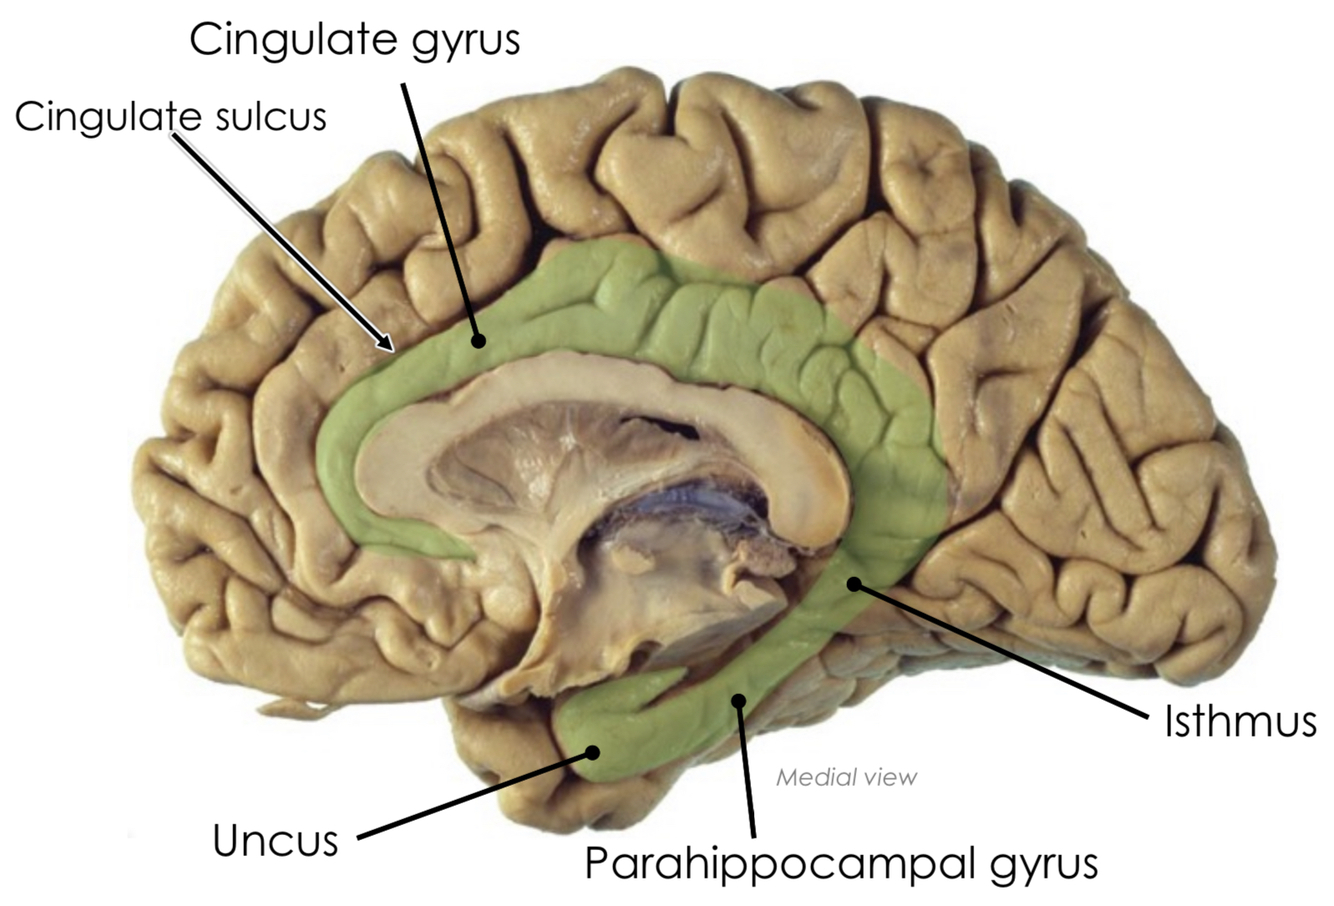

What is the isthmus?

A narrowing of the cingulate gyrus where it is continuous with the parahippocampal gyrus

What is the uncus?

The parahippocampal gyrus hooks upon itself anteriorly to form a bump called the uncus

Where is the cingulate gyrus located?

Below the cingulate sulcus and above the corpus callosum